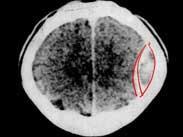

• 出血性腦卒中

628健康網為您分享有關出血性腦卒中的癥狀,出血性腦卒中的治療方法,出血性腦卒中的預防知識,出血性腦卒中的癥狀圖片,出...